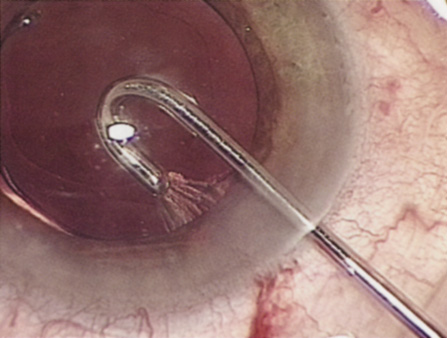

Although slit-lamp examination can give the ophthalmologist an excellent estimate of endothelial health, sometimes a formal assessment of the corneal endothelial cell density is helpful (Fig. 4). This information is most likely to be helpful in advising patients who may be at greater risk of postoperative corneal decompensation. Specifically, patients with cornea guttata, previous ocular surgery, history of blunt ocular injury,56 exfoliation syndrome,57 iridocorneal-endothelial syndromes,58 or a history of glaucoma59 are known to have reduced endothelial cell counts. Patients with a history of acute angle closure are at particular risk because each episode of elevated intraocular pressure can damage endothelial cells.60

There are qualitative and quantitative methods for endothelial cell evaluation. Cell density can be measured directly with an endothelial cell camera. The surgeon also should view the photograph and qualitatively estimate the regularity of the endothelial cell mosaic. Some instruments calculate a coefficient of variability and percent of hexagonal cells.

When an endothelial cell camera is not available, qualitative assessment of count and cell morphology can be accomplished at the slit-lamp using a technique called specular reflection.61 The ophthalmologist focuses a narrow parallelepiped on the corneal epithelium, directing the beam at the periapical cornea from a 45-degree angle. The slit beam is moved slowly from side to side until the bright corneal reflex strikes the examiner's view from the epithelial surface reflection (first Purkinje-Sanson image). On high magnification, the examiner should focus on the endothelial surface just next to the bright reflex. The image of the endothelial mosaic will come into view. The surgeon can make a qualitative assessment of the cell density and degree of regularity. With practice, these estimates can be surprisingly accurate.

The implications of a reduced endothelial cell count are primarily prognostic and can provide the surgeon with more information to help counsel the patient about the risk of corneal decompensation with cataract surgery. Gentle phacoemulsification without triple procedure is recommended when cornea is clear and compact, given that a significant number of patients may be able to avoid a corneal transplant despite uncountable cell densities. However, these patients should be advised that they may be at an increased risk of requiring a corneal transplant.